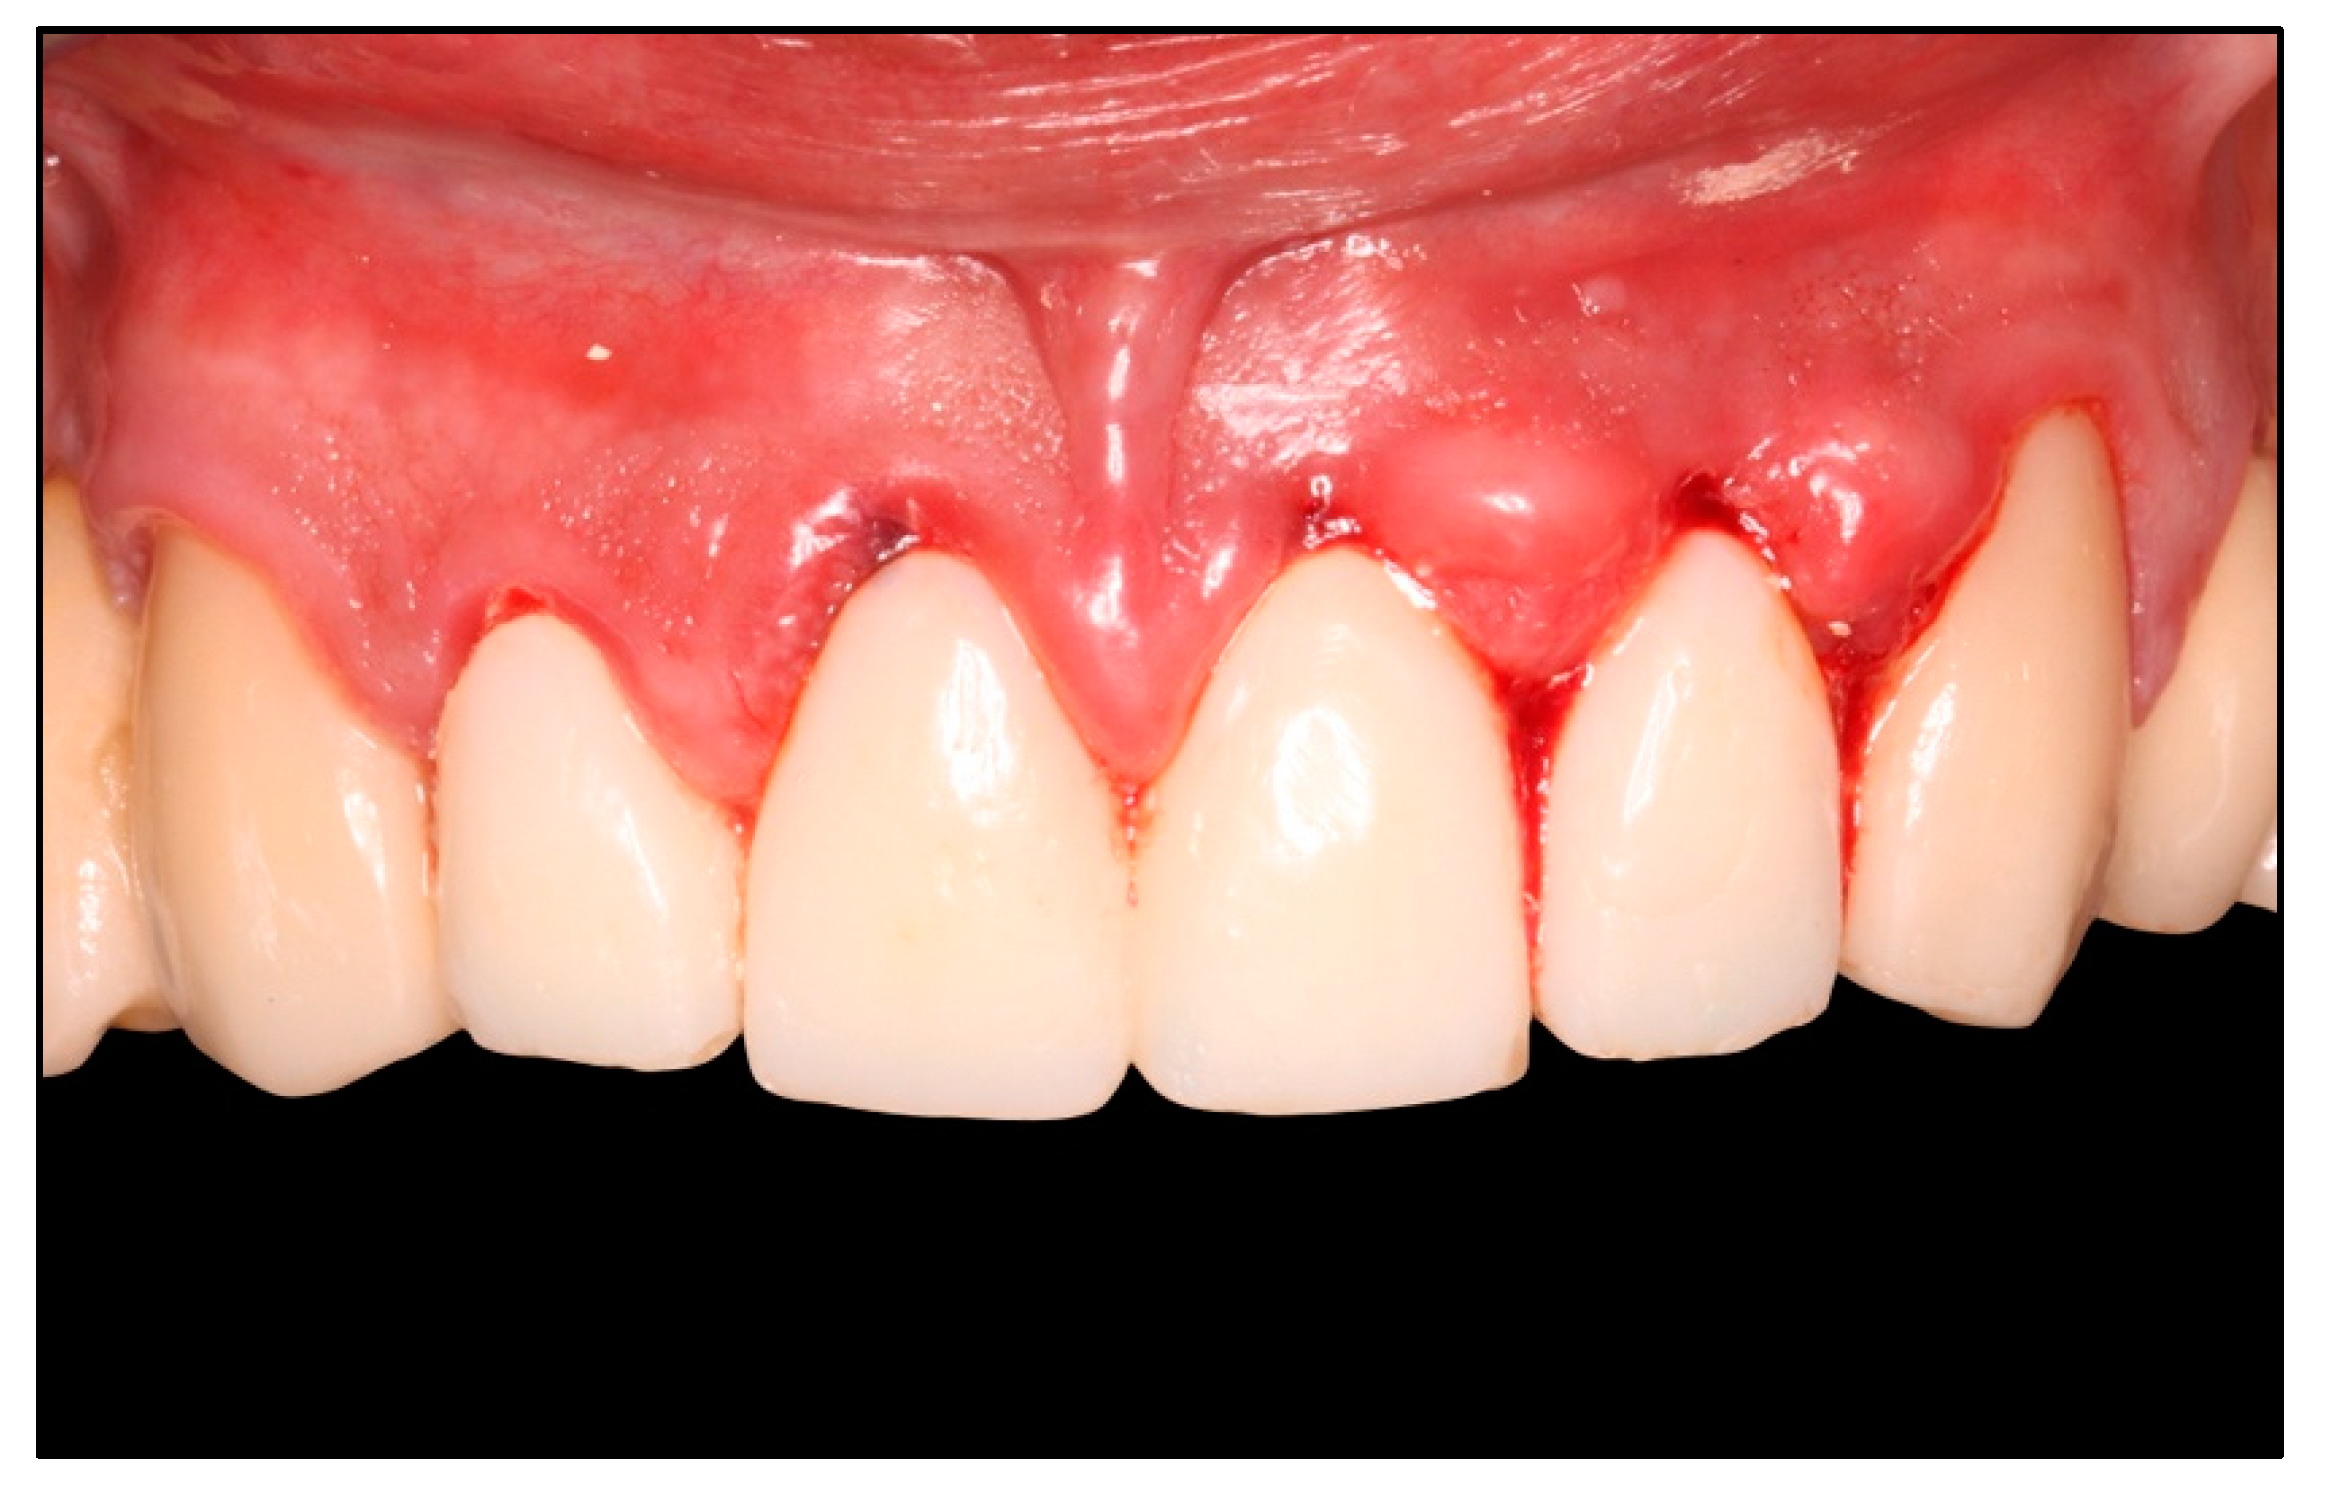

3. Results